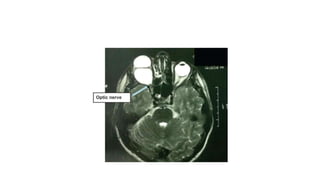

Compressive lesion,tumor ,pitutary adenoma

MS lesion